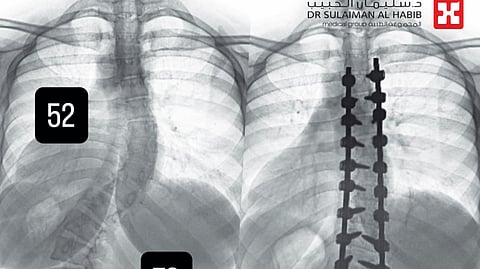

وأجرى لها الفريق الطبي، حزمة من التحاليل والفحوصات الطبية الدقيقة، التي بينت إصابتها بحالة انحراف بجنف درجته "52" بالفقرات الصدرية وآخر بدرجة "72" في الفقرات القطنية، ودرس الفريق الطبي الحالة على ضوء نتائج الفحوصات والتحاليل، وخلص إلى ضرورة التدخل الجراحي لعلاج العيوب، والحد من المضاعفات، وأخضعت الفتاة لعملية جراحية، تم فيها تقويم العمود الفقري بعدد "26" من البراغي والقضبان المعدنية من التايتانيوم والكوبالت كروم والطعوم العظمية الصناعية وتثبيت ودمج الفقرات، وشارك في العملية التي استمرت لـ"6" ساعات، فريق تخدير وتمريض متمرس، واستخدمت فيها مجموعة من أحدث الأجهزة الطبية، التي ساهمت مع الكوادر الطبية عالية الكفاءة والتأهيل بالمستشفى في إنجاحها، ونقلت المريضة إلى جناح التنويم بعد العملية، حيث بدأت في التحسن بشكل متسارع بعد خروجها من غرفة العمليات، إذ استطاعت الوقوف والمشي خلال "24" ساعة، مع فريق العلاج الطبيعي المتمرس، كما أن طولها مع النجاح الكبير للتعديل زاد نحو "4" سم، وخرجت من المستشفى وهي بصحة جيدة، وتوقع أن تستعيد كامل القدرة على الحركة الطبيعية لاحقاً.